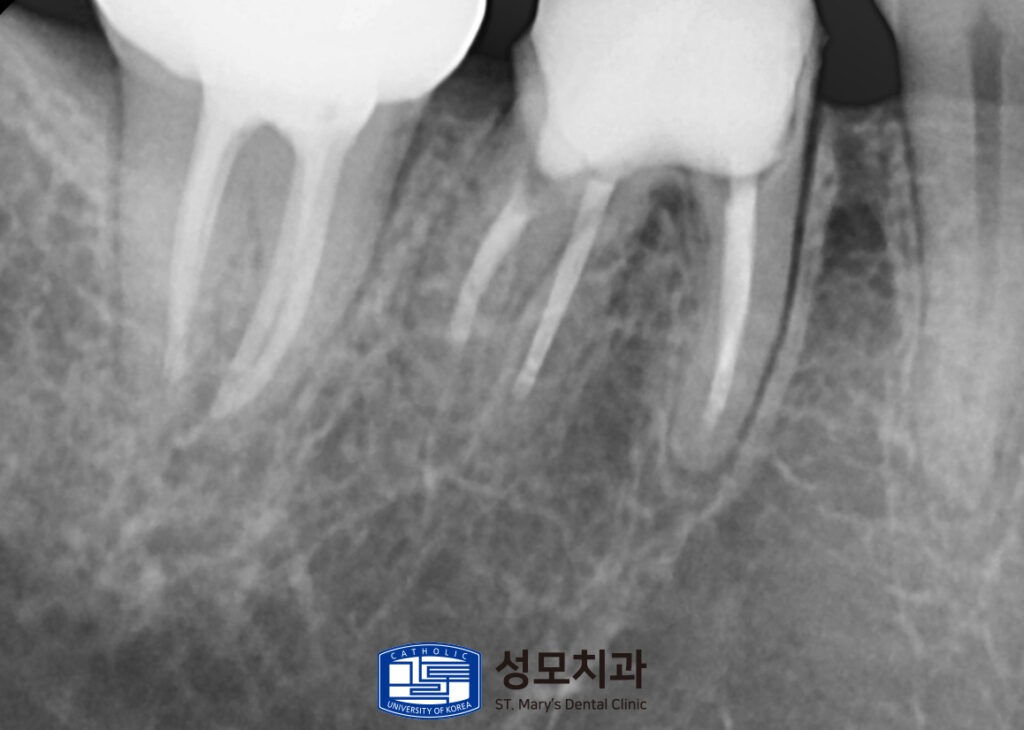

추가로 음식물이 들어가거나 오염되는 것을

막기 위해 임시재료를 매우고

내부 확인을 위해서 작은 X-ray를

촬영하여 파악해 보았습니다.

3. 치료 전 사진

기존에는 신경치료가 부분적으로만 진행된 채

수복물을 진행한 상황이었고

기존 보철물을 수복한 틈새에서

미세한 틈이 발생하였고 이로 인해서 내부에

2차적인 문제가 발생하였습니다.